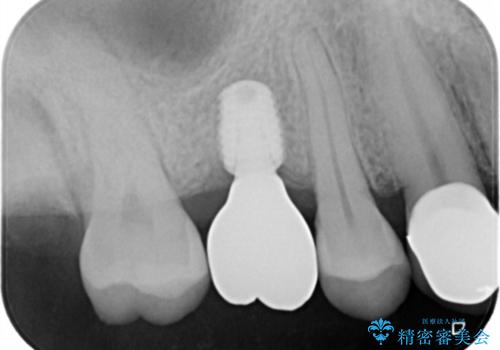

- 右上6番の歯の欠損部の治療を希望され来院された患者様です。

インプラント治療を希望されたので、インプラントとセラミッククラウンでの治療を計画しました。

歯の欠損部への治療には入れ歯・ブリッジ・インプラントという治療が選択されますが、インプラント治療は天然歯を削ることなく治療を行うことが出来ます。